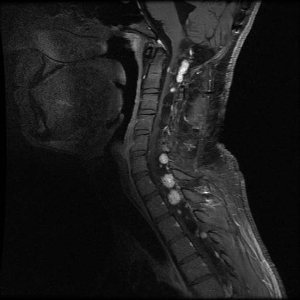

Hemangioblastomas are the most common disease manifestation in patients with VHL, affecting more than 70% of individuals. A prospective study assessed the natural history of hemangioblastomas.[16] The mean age at onset of central nervous system (CNS) hemangioblastomas is 29.1 years (range, 7–73 y).[17] CNS hemangioblastomas were most commonly seen in the cerebellum (45%), spinal cord (36%), cauda equina (11%), and brain stem (7%).[18] While sporadic hemangioblastomas are generally solitary in nature, the VHL-associated CNS lesions are often multifocal. After a mean follow-up of 7 years, 72% of the 225 patients studied developed new lesions.[18] Figures 2 and 3 depict cerebellar and spinal hemangioblastomas, respectively, in patients with VHL.

Figure 3. Hemangioblastomas are the most common disease manifestation in patients with von Hippel-Lindau disease. Multiple spinal cord hemangioblastomas are shown.